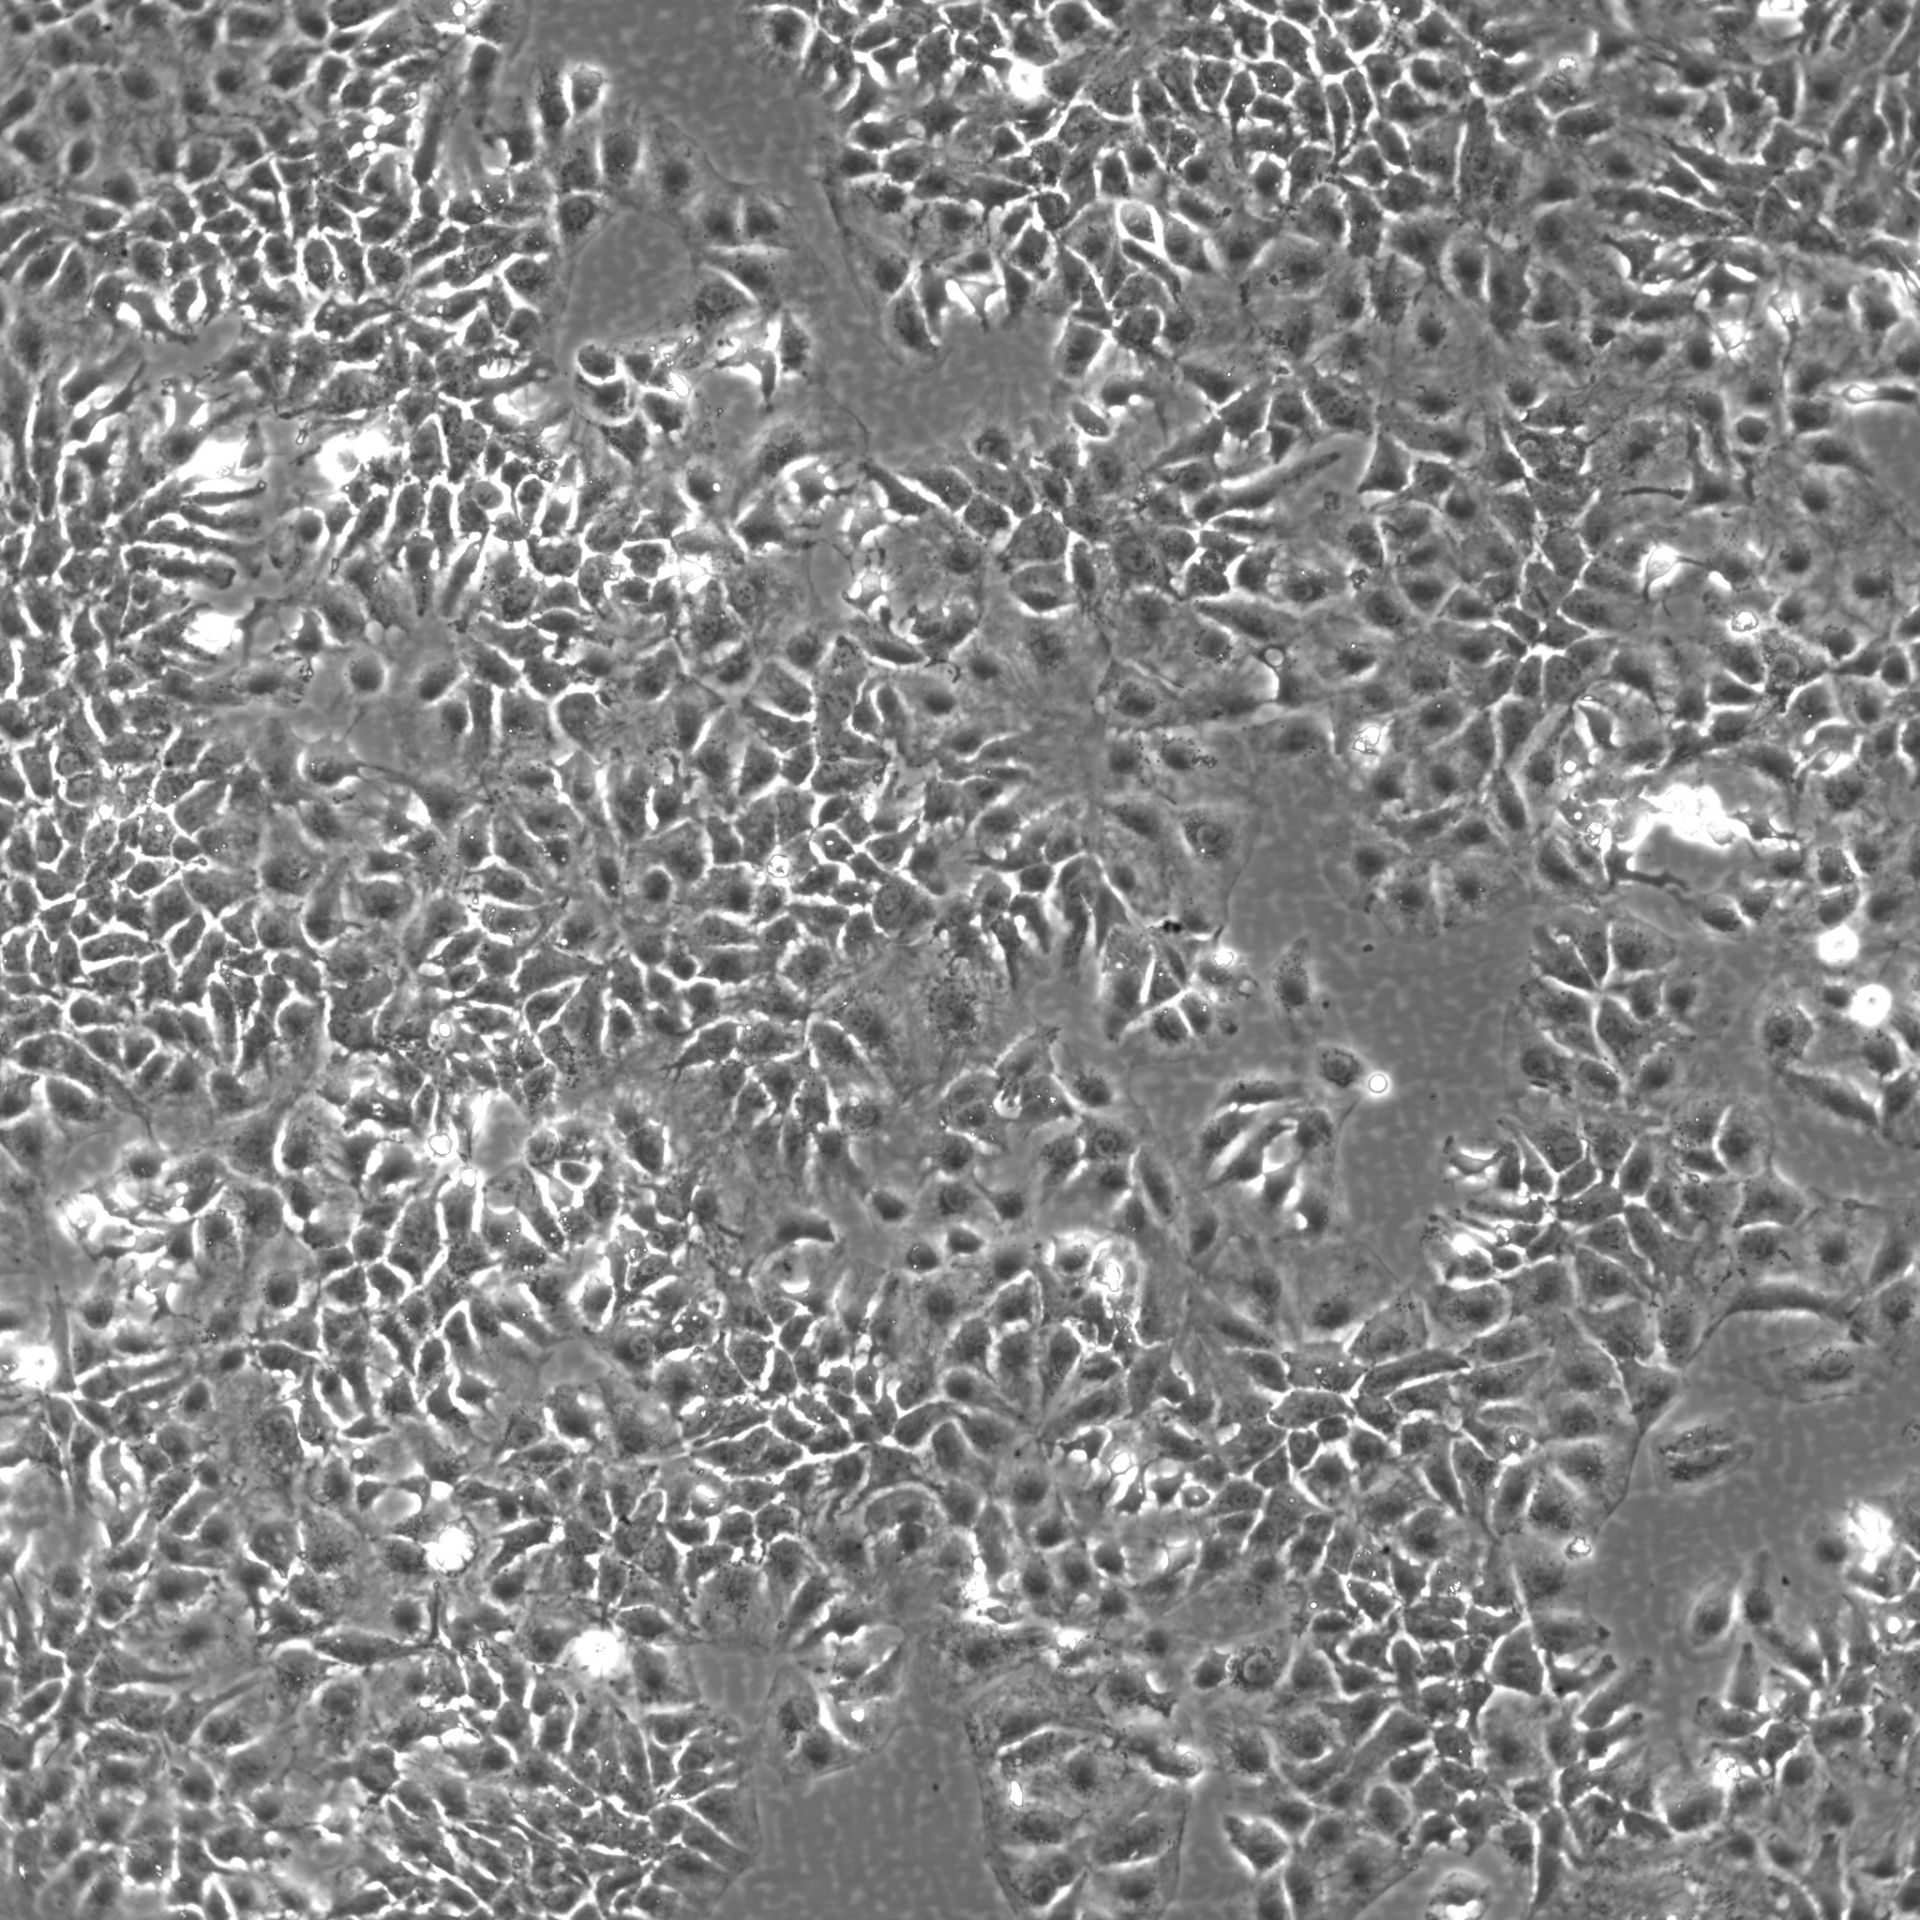

Morphology: Epithelial-like

Growth Properties: Adherent

Description: HuH7 was established in 1982 by Nakabayashi et al. from a 57-year-old Japanese male with well differentiated hepatocellular carcinoma.